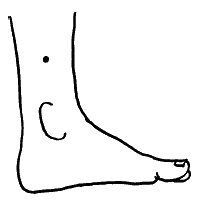

Нередко на коже появляются депигментированные участки — витилиго, а кожа стоп и ладоней может приобрести желто-оранжевый цвет.

Грубые, шершавые локти и пятки, которые многие безуспешно трут пемзой и пытаются смягчить кремами, — тоже признак гипотиреоза на почве йододефицита.